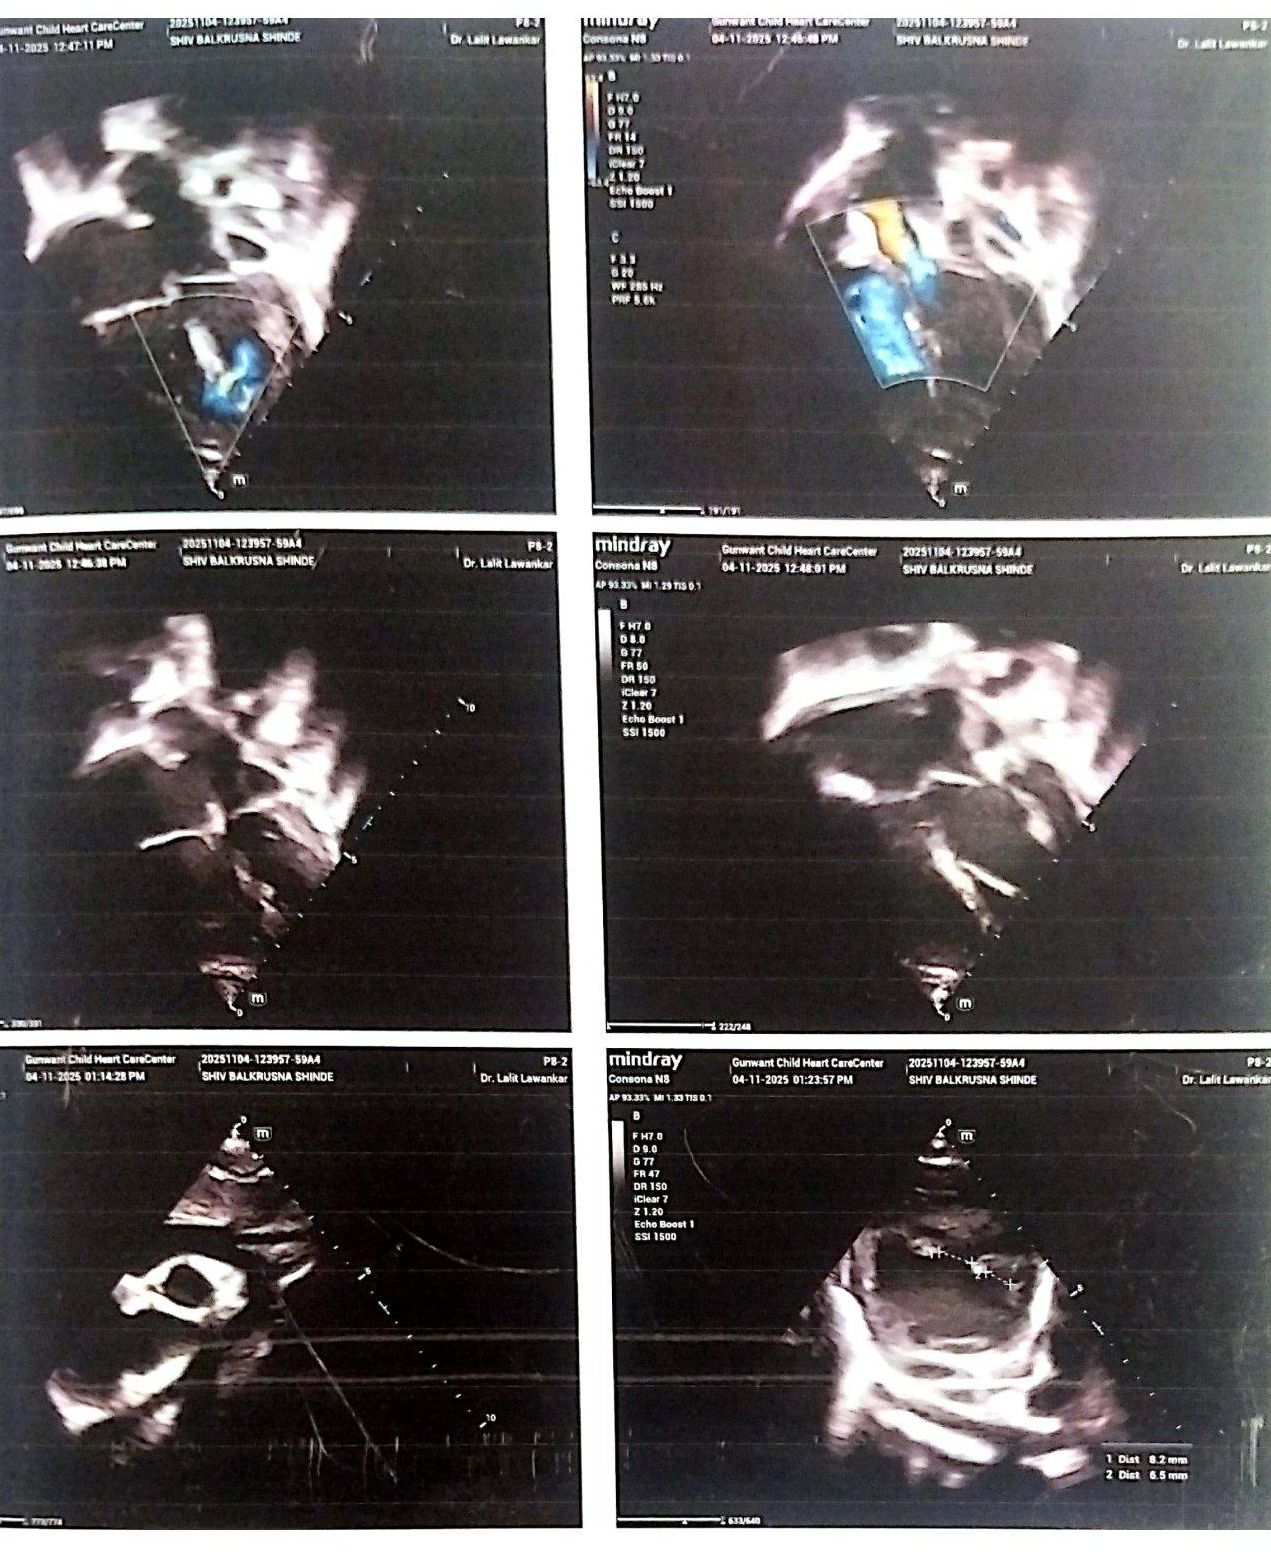

Case of Three Posterior Trabecular VSD ANM

This is to certify that Mast.Priyansh Balkrushna Shinde age 6 months male is a known case of Three Posterior trabecular VSD ANM two midmuscular VSD 8,6MM – Large OS ASD 8mm. He is taking treatment in KIMS Manavata Hospital, Nashik. He has been advised for VSD Surgical closure.